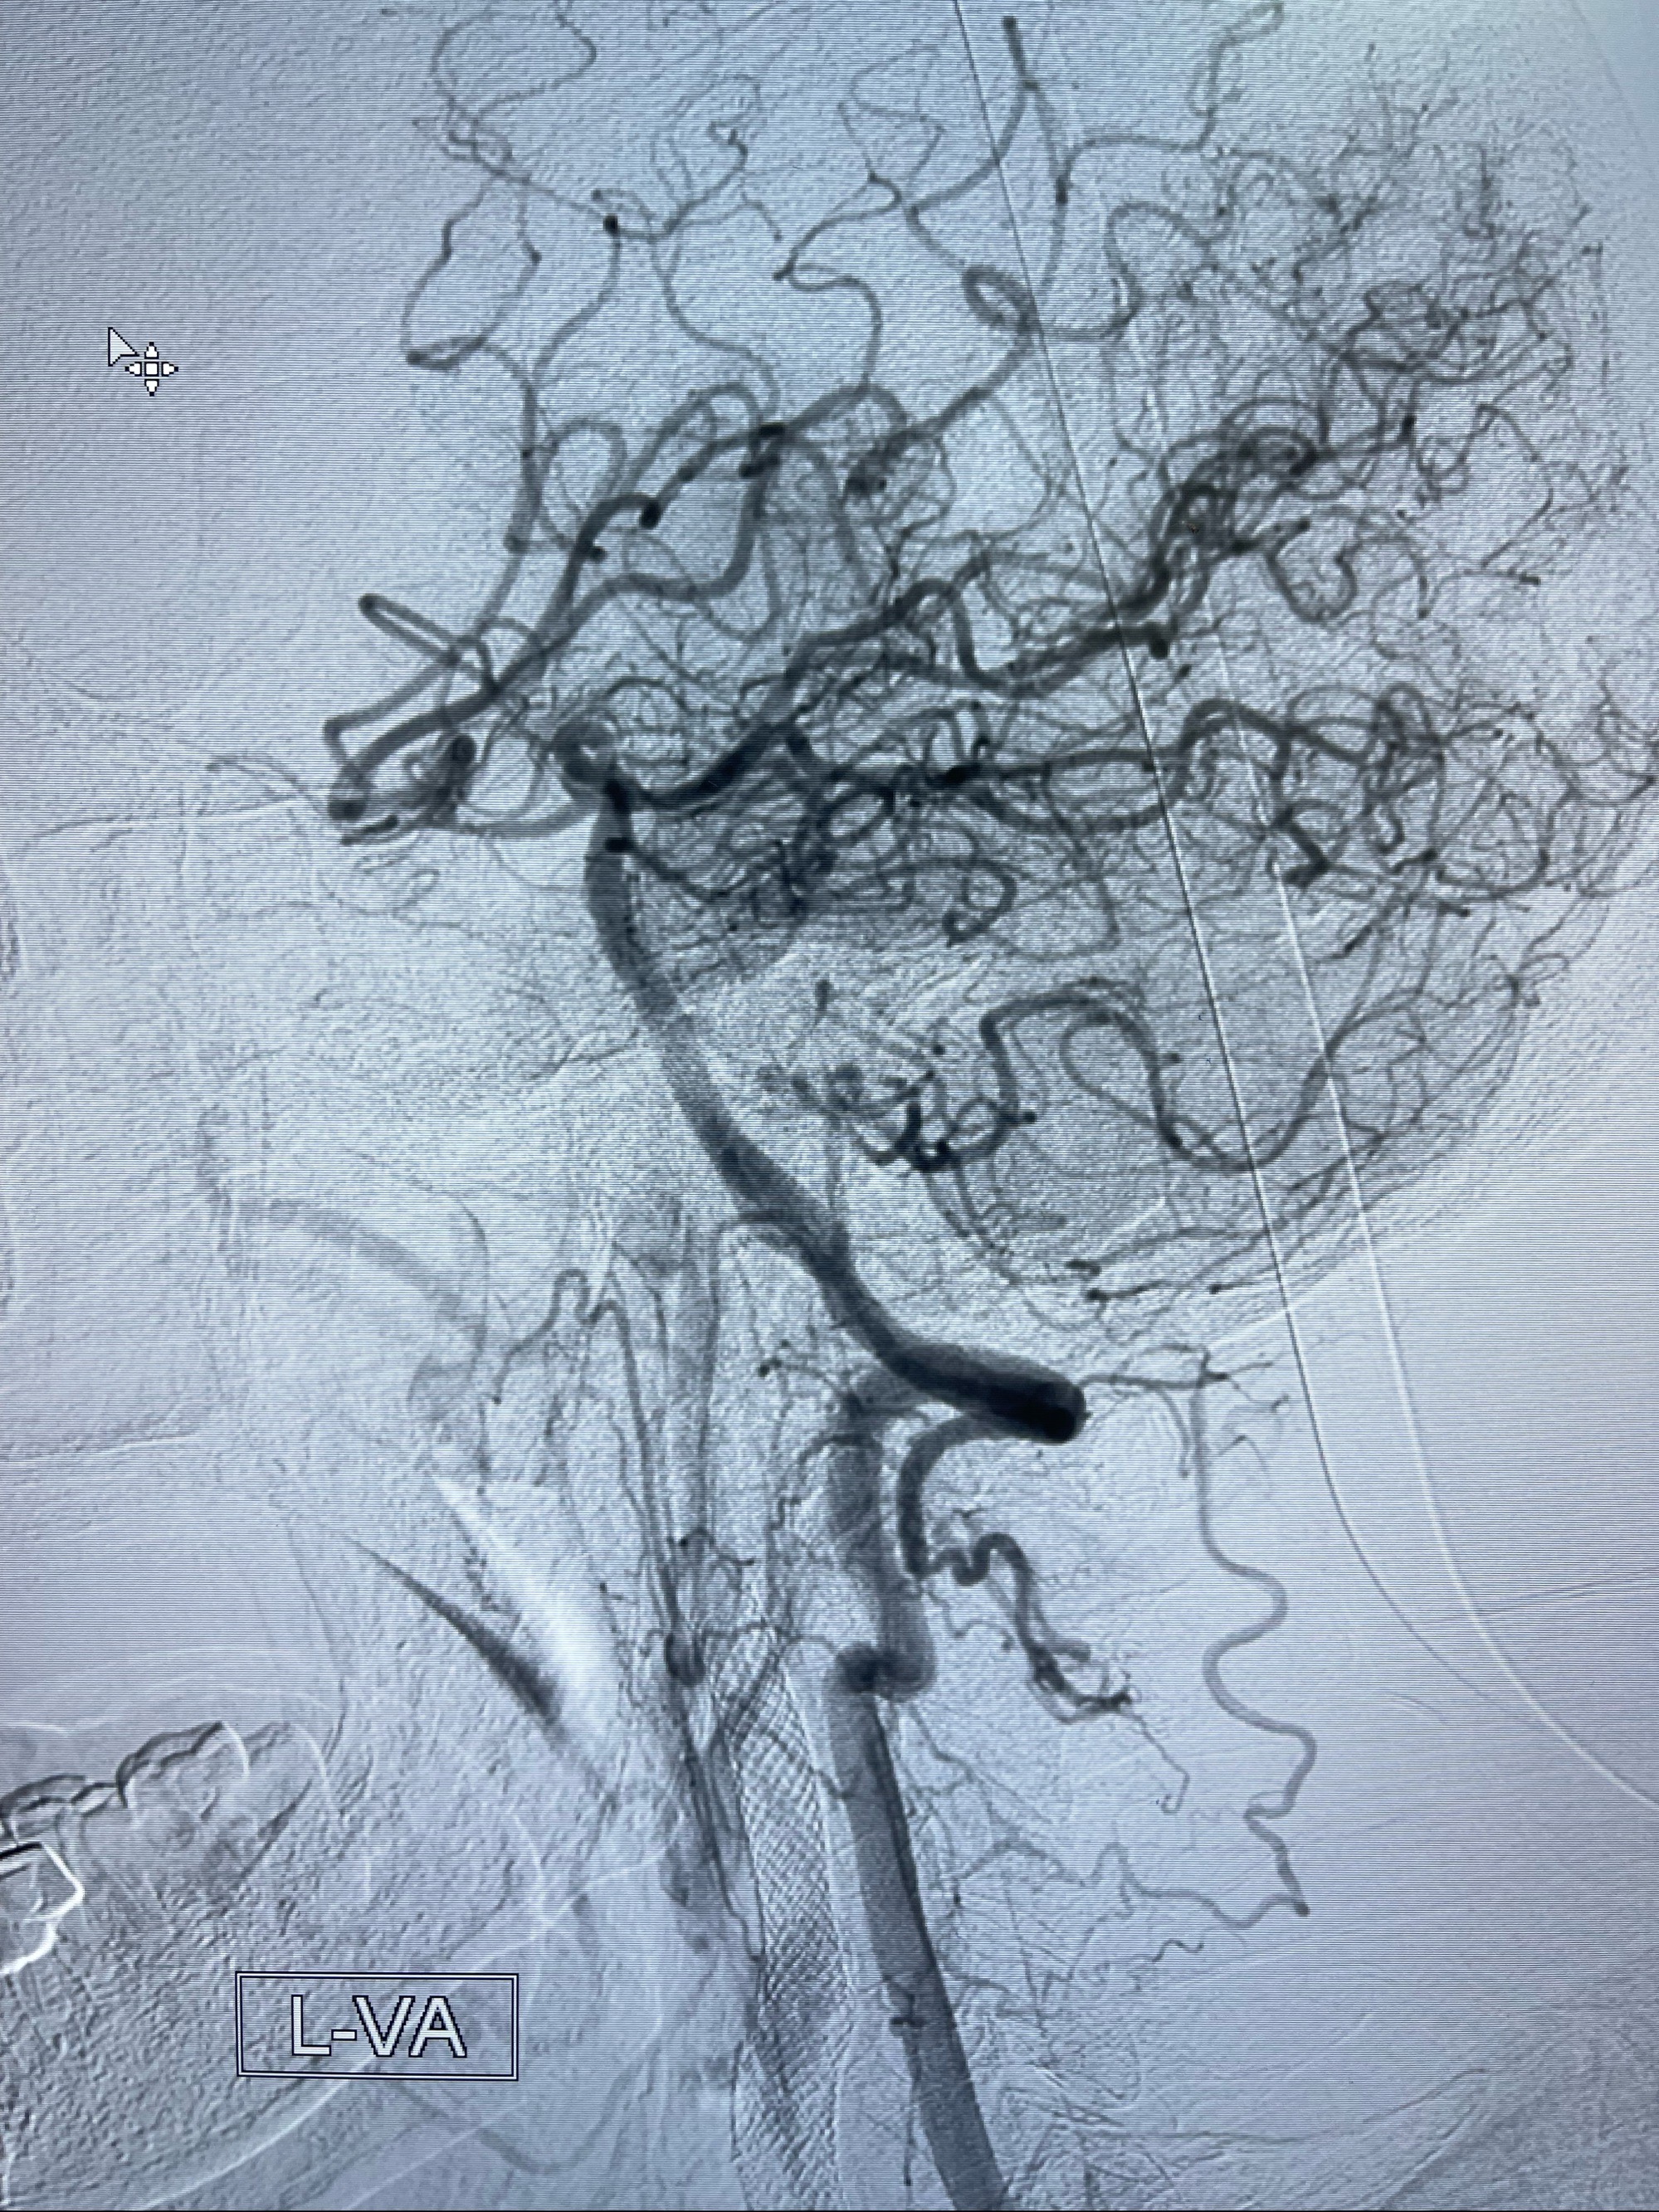

2023-07-10DSA:右侧颈内动脉岩骨段夹层伴中偏重度狭窄改变,左侧颈总动脉闭塞、右侧颈外动脉由右侧肋颈干甲颈干吻合代偿

左侧椎动脉可见代偿显示左侧前循环